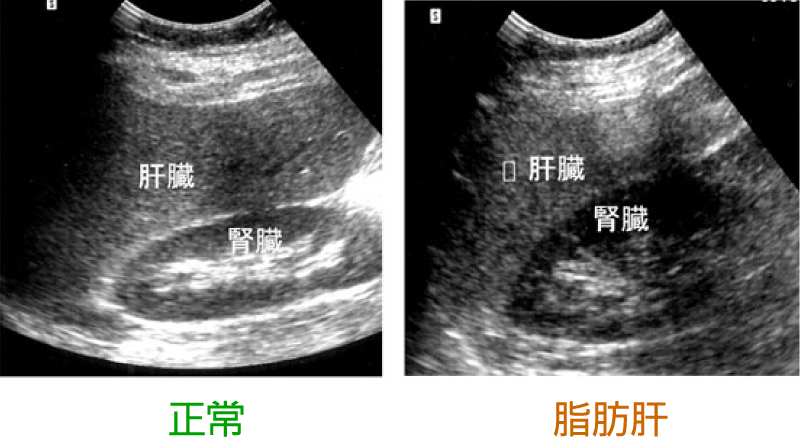

肝臓は超音波検査が有用な臓器です。肝がん、肝血管腫のような良性の肝腫瘍の診断、脂肪肝(画像)が診断できます。